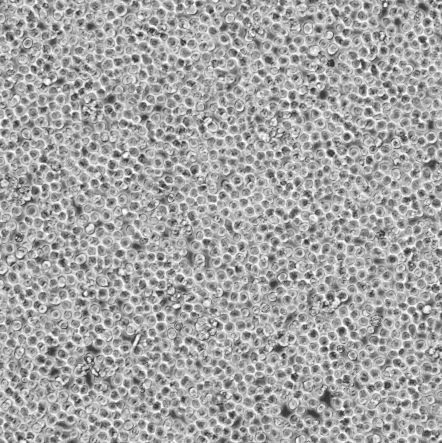

细胞名称:MOLM-14_人急性髓系白血病细胞

细胞形态:圆形细胞